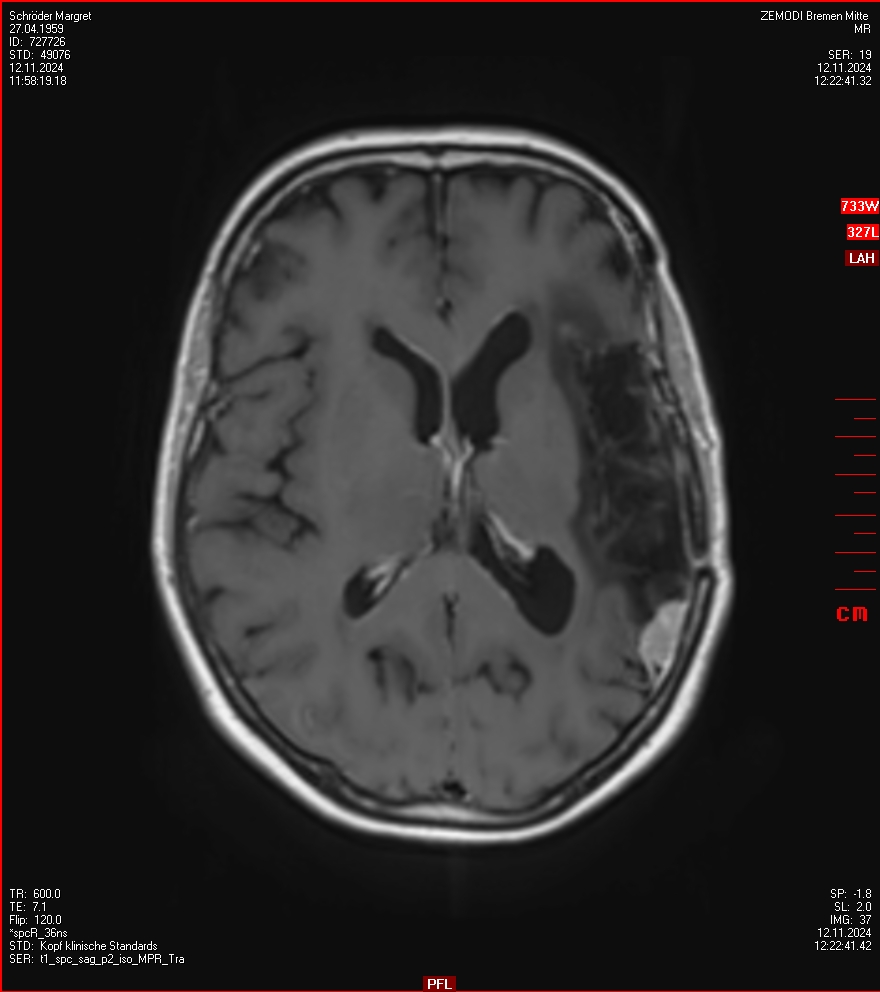

MRT vom 12. November 2024

So nun ein paar neue Bilder aus meinem Kopf. (Durch klicken bekommt man eine größe Ansicht eines Einzelbildes).

Die letzten drei Bilder Zeigen aus meiner Sicht den Tumor, der im Jahr 2021 bestrahlt wurde.

Ich denke, in den letzen 12 Monaten sind da ein paar Rezidive gewachsen,  vor 12 Monaten waren sie auch schon zu erkennen - vorher noch nicht. Nun hoffe ich auf den Rat des Spezialisten. Hoffendlich kann man etwas machen.